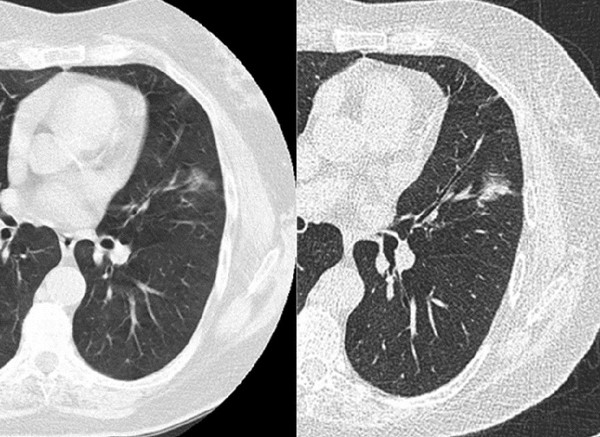

单纯性磨玻璃结节(左)及混合性磨玻璃结节(右)(图片来自于I-ELCAP本研究)

63岁老年女性,出国看病服务机构了解到持续存在的单纯性磨玻璃结节,最终诊断为恶性。左图)薄层CT提示左肺上叶14mm的单纯性磨玻璃结节,箭头所指 右图)一年后随访薄层CT提示病变无明显改变,该患者接受左肺上叶切除术,病理诊断为支气管肺泡癌,肺腺癌的一种亚型(小编经过弗洛雷斯主任同意, 编辑引用该图为读者参考)

64岁老年男性,有吸烟史。薄层CT提示两个单纯性11mm局限性的磨玻璃结节,位于右肺下叶。两个结节病理诊断不一致。在轴位图片的基础上增加冠矢状位图片即可将这些结节进一步分为结节样及分叶样密度,或者是均匀密度。左边的结节表现为混合亚型腺癌,含有支气管肺泡成分。右边的结节则是上皮脱落的间质性肺炎。因此,结节的形状对于检查的预后预测价值有重要作用。(小编经过弗洛雷斯主任同意, 编辑引用该图为读者参考,参见2)